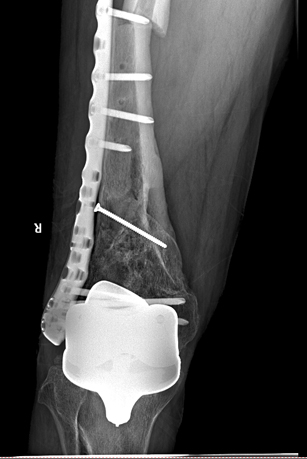

在手术之前,首先做股骨全长薄层扫描CT,将患者股骨影像及数据搜集并记录下来,通过3D打印技术制作出一个1:1比例的股骨“复制品”,它的直径、长短、髓腔形态都与患者真实情况完全相符,甚至患者骨骼上每一块凹陷与凸起,每一点纹理和痕迹都呈现得一清二楚。然后通过在体外对模型进行模拟手术操作,准确制订出了髓内钉的入针点、长度、直径,精确计划出远端锁钉准确位置。手术时,按着术前的设计顺利完成了手术,大大缩短了手术时间,减少了对患者的创伤。术后影像骨折解剖复位,锁钉位置精准无误,术后患者顺利康复。

术后影像